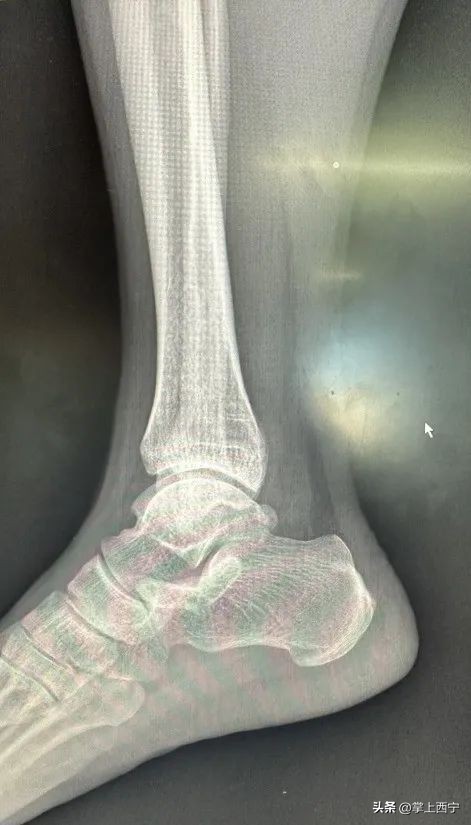

↑ 术前CT检查

经过骨二科鲍义章主任和医师团队的进一步诊察,诊断为距骨软骨损伤并收治入院。患者入院后,医护人员为患者进行了充分的术前检查,经科室医师团队进行周密的病例讨论后,完善了各项术前准备,为患者施行了自体骨软骨移植术治疗距骨软骨损伤。

出现上述情况可去正规医院创伤骨科与足踝外科门诊就诊,给予完善查体,了解足踝部的活动度是否正常,有无固定的压痛部位,除此之外,还需结合影像学检查,其中 MRI(核磁共振)检查 可以更准确地显示出关节软骨损伤的面积大小以及受伤深度等情况,为进一步治疗提供依据。